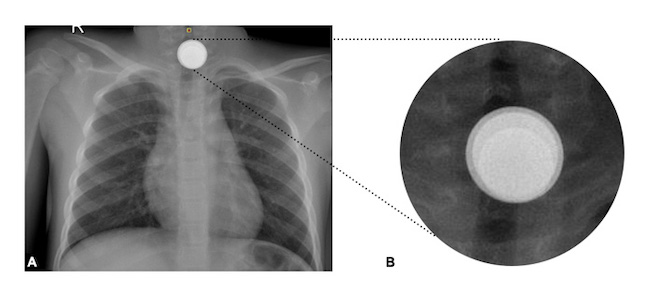

A previously well 5-year-old girl presented to the emergency department with an acute onset of sialorrhea, odynophagia, and nausea. Vital signs were normal and no other abnormalities on physical examination were found. There was no significant medical, social, or family history. Given the child’s age group and symptoms, ingestion of a foreign body was suspected. An anteroposterior cervico-thoraco-abdominal radiograph (CTA X-ray) was obtained revealing a foreign body in the upper third of the esophagus which seemed to show a double rim sign, although an irregular layout was noted (Fig. 1a). Suspecting a button battery sign, immediate endoscopic removal was indicated. During the preoperative nasopharyngeal swab testing for SARS-CoV-2, the patient experienced an acute episode of emesis, expelling a 1-euro cent coin (cent €). After this, the child became asymptomatic. Despite the initial suspicion of a button battery sign and the patient is asymptomatic, a close inspection of the CTA X-ray with digital magnification demonstrated that the image of the foreign body was formed by the superimposition of three circumferential objects of different sizes (Fig. 1b).

Unusual radiographic findings have been documented regarding esophageal foreign bodies, such as ingested coins with a sagittal orientation as if they were in the trachea 9-11. Ormeño et al. (9, reported a case of two coins impacted in the esophagus also simulating the double rim image of a button battery. In our case, the radiological finding was not a defined double ring but rather the superimposed silhouettes of three round objects of different sizes, arranged in the same way as celestial bodies do during a lunar eclipse (Fig. 3a). This finding (Fig. 1b*) created by the radiological arrangement of the coins in the patient's esophagus is a novel radiological finding that may alert the physician to the presence of multiple coins and distinguish them from a button battery, enabling the best therapeutic choice.